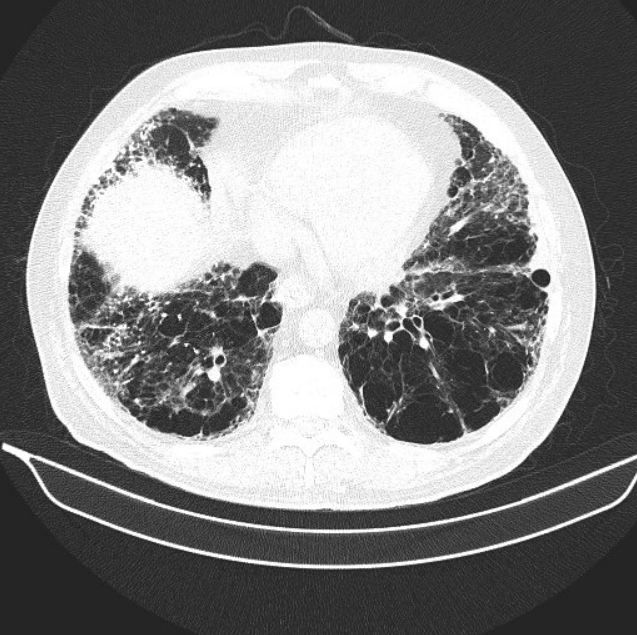

Figure 3.

The primary care physician was concerned about the possibility of interstitial lung disease or pulmonary malignancy. He sent the patient for a high resolution CT of the chest (Figures 1-3; please click figures to enlarge) as well as pulmonary function testing (Table, see next page).

Flows show evidence of moderate obstruction. Lung volumes are normal. Diffusing capacity is very severely reduced. These PFTs, in the absence of additional clinical information, might be interpreted as consistent with COPD. However, the marked reduction of DLCO-which is way out of proportion to the reduction in flows, should clue the clinician into the possibility of a mixed defect. In this patient both the severe emphysema and the pulmonary fibrosis seen on CT scan are negatively affecting the lung’s ability to diffuse CO into the bloodstream, which accounts for the very severe reduction in diffusing capacity. Interestingly, fibrosis and COPD actually counteract each other in flows and volume. Pulmonary fibrosis will actually increase the FEV1/FVC ratio, and COPD will reduce it. Alternatively, pulmonary fibrosis typically reduces lung volumes symmetrically, while COPD can raise TLC and FRC due to hyperinflation. Thus, when patients have combined pulmonary fibrosis and COPD, often lung volumes and flows are relatively preserved, and diffusing capacity is markedly decreased, as seen in this patient.